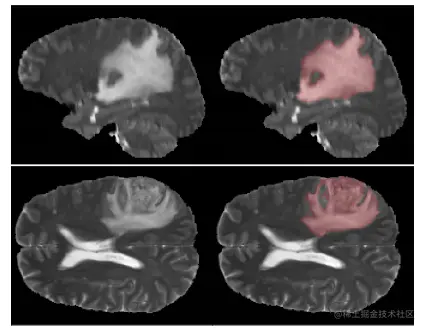

为了评估我们的网络性能,我们使用BRATS18脑瘤分割数据集。它包含175名恶性胶质瘤和低级别恶性胶质瘤患者的MRI扫描。图像分辨率为240×240×155像素。ground truth标签是由神经放射学专家创建的。数据集的一个示例如图2所示。

图片

图2:MRI切片的例子以及分割的ground truth